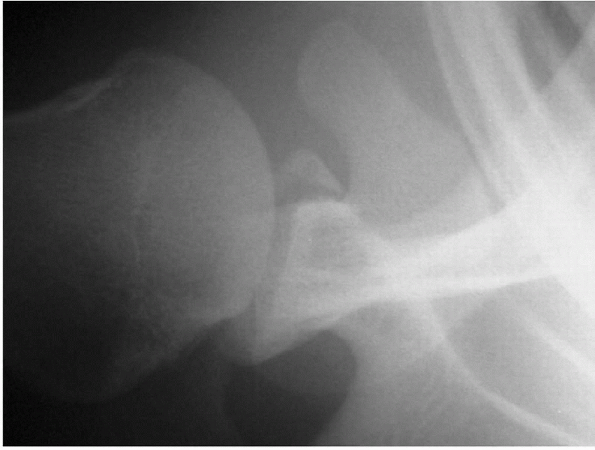

![]() |

Figure 17-6 Radiograph of a bony Bankart lesion.

anterior-inferior glenoid: the impression fracture or the avulsion

fracture. The compression Bankart lesion is secondary to compression of

the anterior-inferior bony articulation of the glenoid by the humeral

head. Repeated episodes of instability create the “inverted pear”

lesion, as well as a typical bony Bankart. Investigators in the past

have recommended a coracoid transfer if the glenoid rim fracture

comprised 25% of the anterior-posterior diameter of the glenoid. Burkhart et al. (2002)

described the containment of the humeral head by the glenoid as a

result of two geometric variables: (a) the deepening effect of a wire

glenoid due to the longer arc of its concave surface and (b) the arc

length of the glenoid itself. They caution that if the bony fragment is

excised or if there is an inverted pear-shaped glenoid, arthroscopic

techniques without a bone augmentation procedure may be predisposed to

failure (Fig. 17-7).